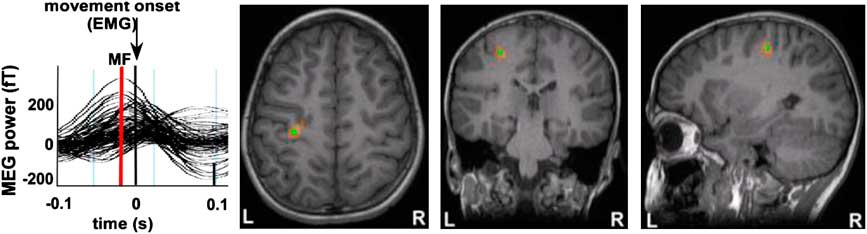

Fig. 2 The schematic depicts the reaction time task and corresponding motor measurements (cortical motor field response and EMG onset).

The event-related beamformer (ERB) (Cheyne et al., Reference Cheyne, Bostan, Gaetz and Pang2007) was used to localize the cortical responses known to accompany the transient finger movements, based on scalar beamformer algorithm (Cheyne et al., Reference Cheyne, Bakhtazad and Gaetz2006; Pang et al., Reference Pang, Drake, Otsubo, Martineau, Strantzas, Cheyne and Gaetz2008). The inner skull surface was used to create the multiple spherical head model. EMG onset was marked manually off-line and data re-epoched to −1.5 to 1 s with EMG onset as time = 0 ms after bandpass filtering from 0 to 30 Hz. Event-related images were computed with 2 mm sampling resolution, using time steps of 5 ms increments preceding and following movement onset (−0.1 s to 0.1 s) and scanned manually to observe peak activity. The motor field (MF) location was defined as the location of motor cortex activity observed at the time-point of maximum power around the time of finger abduction and marked on each subject's raw T1 volume for further DTI analysis. T1-weighted MR images were co-registered to MEG head coils sensors for spatial localization.

All participants showed activation in the hemisphere contralateral to the side of movement. Activations were localized to the region of the anatomically defined hand area or “knob” (Yousry et al., Reference Yousry, Schmid, Alkadhi, Schmidt, Peraud, Buettner and Winkler1997) (Figure 4). Activity reached maximal amplitude in the pre-central gyrus and occurred just before movement onset (between 20 and 80 ms). This point of maximal amplitude was defined as the motor field peak. In all participants, there was also significant activity localized to the motor knob of the ipsilateral pre-central gyrus for both right and left finger movements. Contralateral and ipsilateral source localizations were used as launch points for DTI tractography analyses.

Fig. 4 Motor Field (MF) responses are shown for a representative participant. Source wave forms from peak MF locations were observed following right index finger abduction movements for each individual and show an increase in source power (MF, red line) before EMG onset at time = 0 s. Source localization of these MF peak latencies were superimposed on each subject's MRI and were clearly situated in the contralateral pre-central gyrus (motor “knob”) for each individual. Using these methods, MF locations from primary motor cortex were used as seed points for DTI tractography for each participant in our study.